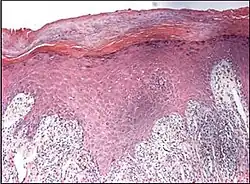

Interface dermatitis with lichenoid inflammation

| Main conditions[2] | Characteristics | Micrograph | Photograph |

|---|---|---|---|

| Generally/Not otherwise specified | Typical findings:[2]

|

||

| Lichen planus | Irregular epidermal hyperplasia with a jagged "sawtooth" appearance, compact hyperkeratosis or orthokeratosis, foci of wedge-shaped hypergranulosis, basilar vacuolar degeneration, slight spongiosis in the spinous layer, and squamatization. The dermal papillae between the elongated rete ridges are frequently dome shaped. Necrotic keratinocytes can be observed in the basal layer of the epidermis and at the dermal-epidermal junction. Eosinophilic remnants of anucleate apoptotic basal cells may also be found in the dermis and are referred to as "colloid or civatte bodies". Whickham striae are usually seen in the areas of hypergranulosis. Vacuolar degeneration at the basal layer may be noted leading to focal subepidermal clefts (Max Joseph spaces). Squamatization occurs as a result of maturation and flattening of cells in the basal layer. It happens in areas of marked hypergranulosis with prominence of the sawtooth pattern of rete ridges. Wedge-shaped hypergranulosis can occur in the eccrine ducts (acrosyringia) or hair follicles (acrotrichia). In the hypertrophic subtype, the associated hyperkeratosis, parakeratosis, hypergranulosis, papillomatosis, acanthosis, and hyperplasia markedly increased with thicker collagen bundles forming in the dermis. Moreover, the rete ridges are more elongated and rounded as opposed to the typical sawtooth pattern. In atrophic LP, loss of the rete ridges and dermal fibrosis is prominent. In vesiculobullous LP, the disease progression is quicker. Hence, some of the distinctive features such as hyperkeratosis, hypergranulosis, or dense lymphocytic dermal-epidermal infiltrate may not be present. LP lesion may resolve with residual hyperpigmentation caused by a persistent increase in the number of melanophages in the papillary dermis.[9] | ![]() | ![]() |